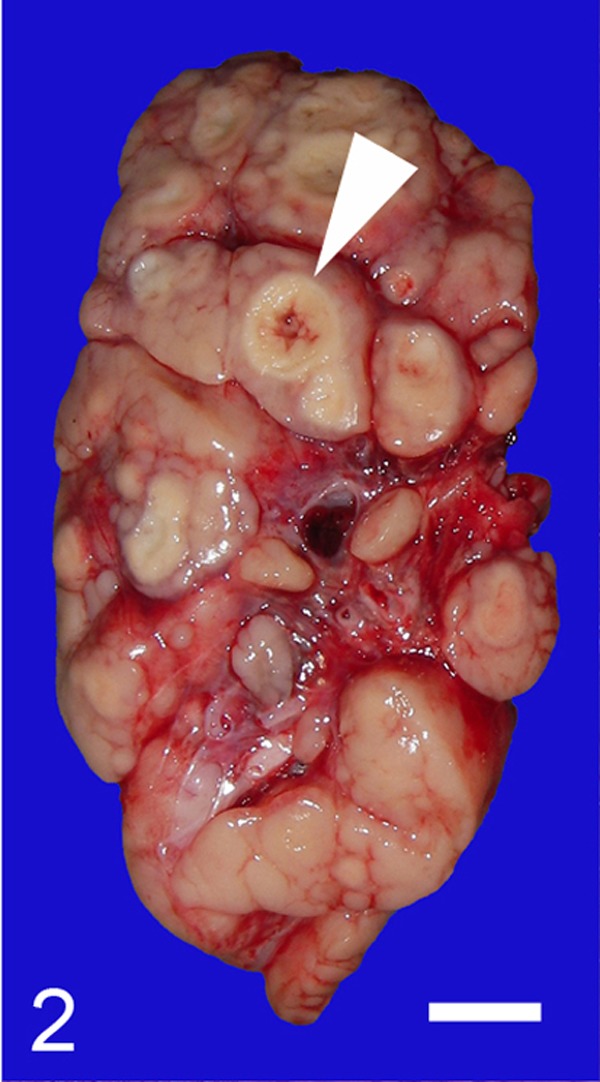

The aborted fetus exhibited a crown-rump length of 47 cm and weighed 10 kg. The fetus presented with growth insufficiency and was emaciated, and a white viscous substance adhered to its external surface. Enlarged superficial and visceral lymph nodes were seen throughout its body, including the axillary, inguinal, mediastinal, bronchial, intercostal, hepatic, splenic, gastric, mesenteric and colonic lymph nodes. The cranial mesenteric lymph nodes were most severely affected and measured approximately 9 × 4 × 4 cm (Fig. 1). Cut sections revealed the multinodular proliferation of homogenous light-tan tissue with occasional central yellowish-white foci (Fig. 2). The liver was diffusely yellowish in color and slightly swollen. About half of the caudate lobe of the liver had been replaced with an aggregate of small yellowish-white nodules, which measured up to 3 mm in diameter. The tonsils were enlarged and exhibited an irregularly roughened surface. White nodules, which measured up to 5 mm in diameter, were scattered throughout the lungs, thymus, spleen and right thyroid gland. The intestinal mucosa was diffusely roughened from the jejunum to the colon, and many minute white nodules were evident in the wall on cut sections. The lungs displayed diffuse atelectasis.

Fig. 2.

Cut surface of a cranial mesenteric lymph node. The lymph node is enlarged and has been replaced with homogenous light-tan tissue and occasional central necrosis (arrowhead). Bar=1 cm.